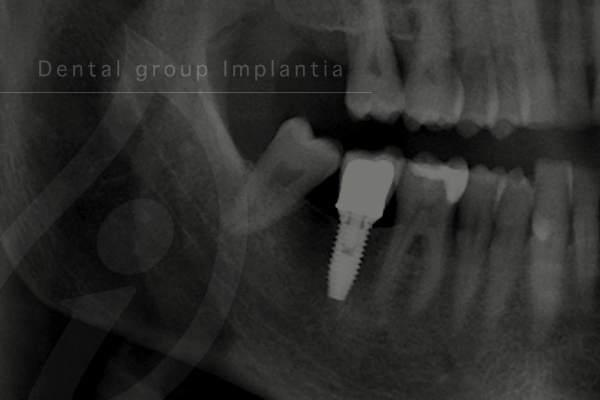

임플란트란?

치주질환이나 외상 등의 이유로 치아가 상실된 경우, 자연치아를 대체해주는 술식 중 하나입니다.